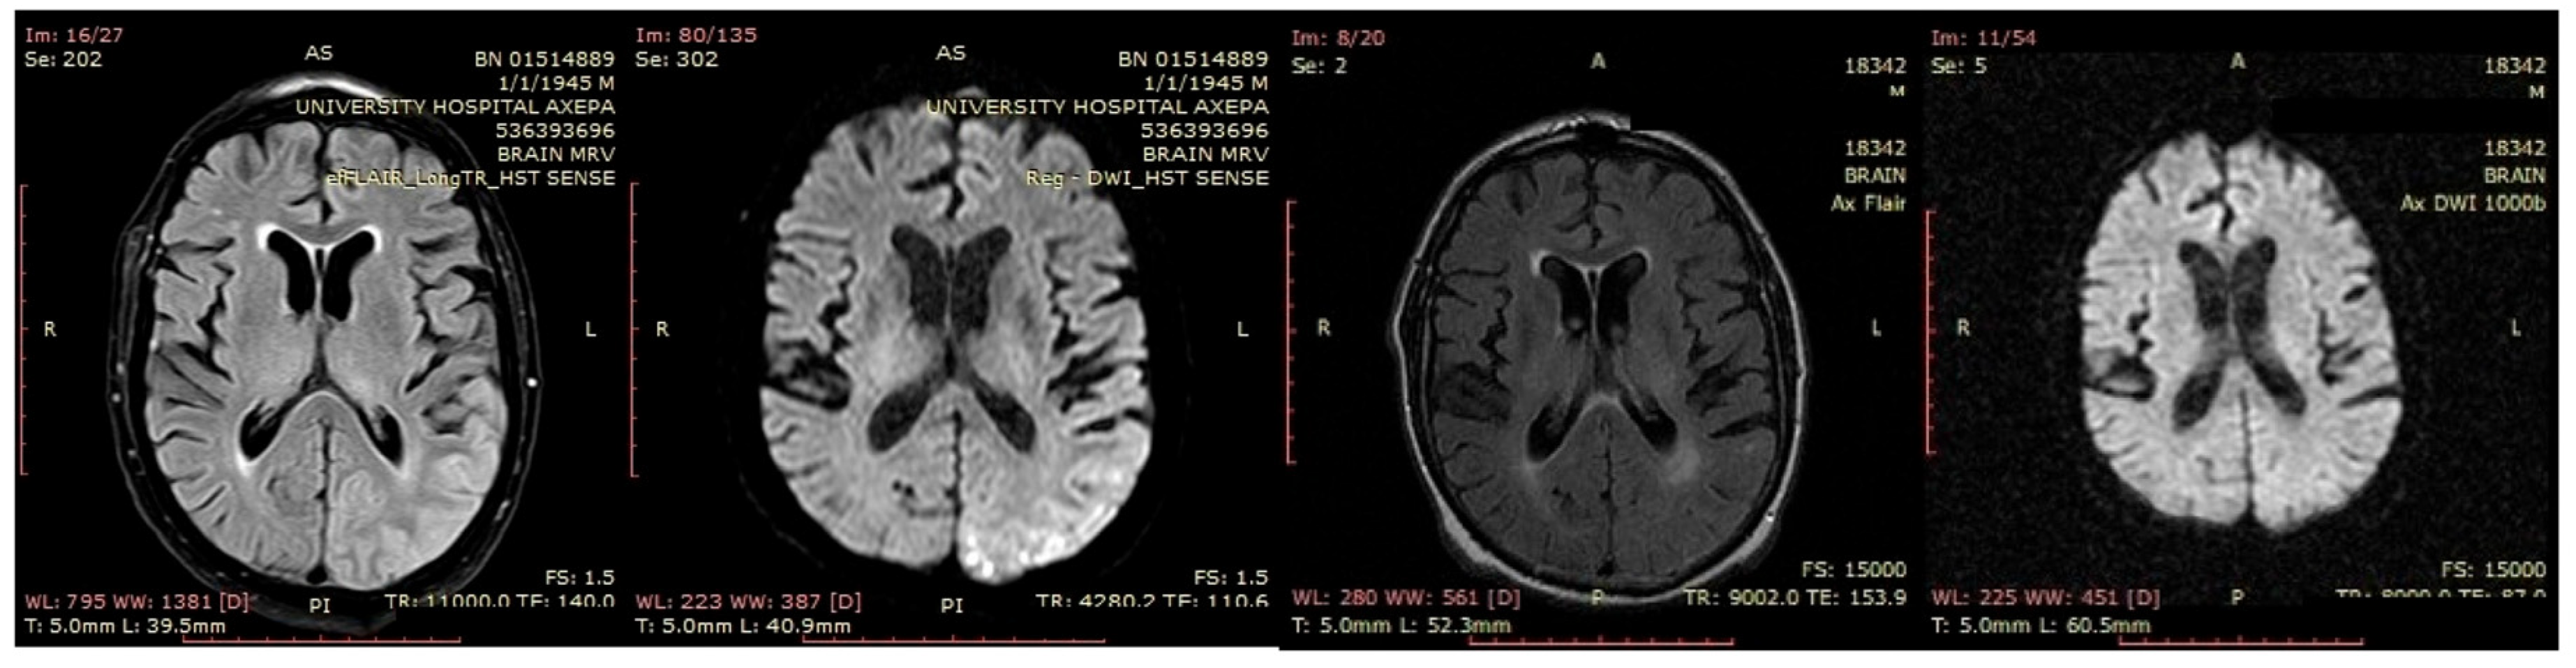

A 70-year-old male was initially diagnosed with MCI. At that time, ACE-R score was 83, and the EEG showed generalized slowing with slow waves (3–5 Hz) predominantly in the frontal–temporal areas (Figure 13A). Two years later, he experienced multiple episodes of unresponsiveness and staring, followed by confusion, along with episodes characterized by fluctuating speech impairment characterized as aphasia, coinciding with febrile illness. EEG recorded continuous multiform sharply contoured slow waves 2–4 Hz over the left frontal–temporal area with transient slow multiform abnormality 4 Hz over the right temporal area (Figure 13B). Brain MRI revealed abnormal signal in the cortex of the left temporal–parietal–occipital areas, attributed to ischemic changes secondary to prolonged epileptic discharges (Figure 14). He was treated with levetiracetam and lacosamide, with clinical improvement, and the subsequent EEG 3 days later revealed isolated sharp waves over the left frontal–temporal area with occasional focal slow waves 2–3 Hz in the left hemisphere (Figure 13C). Six months later, he was reevaluated. Neurological examination demonstrated apraxia, apathy, paraphasia, and positive grasp and palmomental reflexes. Cognitive testing yielded an ACE-R score of 71. MRI abnormality was resolved (Figure 14) and repeat EEG was invariable (Figure 13D). The clinical course, including the resolution of MRI abnormalities and the stabilization of cognitive decline following seizure control, suggested that the epileptic activity was causally related to cognitive impairment in this patient from early on. Consequently, he was diagnosed with focal impaired awareness seizures of left temporal origin, leading to MCI.

Figure 14. From left to right: the first and the second images demonstrated signal abnormality in the cortex of the left temporal–parietal–occipital areas in fluid-attenuated inversion recovery (FLAIR) and diffusion-weighted imaging (DWI), respectively, which resolved in follow-up MRI (third image—FLAIR, fourth image—DWI).